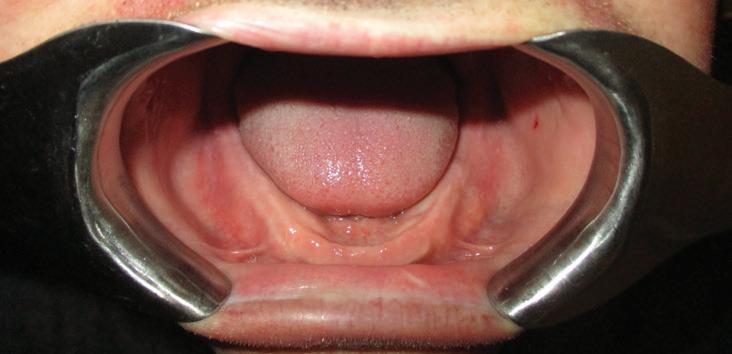

This patient is a 34-year-old male. He works as a dental assistant. His chief concern was, “I have temporary dentures that are six years old. They are discolored and do not fit well. I cannot eat with them.”

The patient was initially injured while playing college baseball when he was hit in the mouth with a baseball. As a result of this injury, the patient lost all of his teeth. This event was six years ago.

Medical History: The patient suffers from anxiety and depression. He is a tobacco smoker, and has smoked half a pack a day for 10 years.

Rx. History: Xanax, Effexor

Implants were placed in areas of nos. 22 and 27. Implant no. 22 was Nobel Replace RP 4.3x11.5 torqued to 42.1 N/cm; implant no. 27 was Nobel Replace RP 4.3x11.5 torqued to 45.0 N/cm. Due to the patient wearing dentures, cover screws were placed and horizontal mattress sutures were placed. (The ends were clipped after the photos.) The patient was seen two days after and was healing well He was very happy with his treatment.